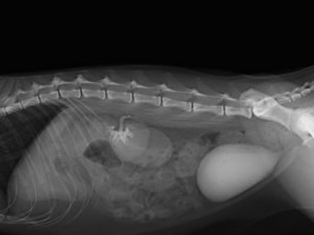

人工尿管(SUBシステム2.0)を設置

尿管結石を取り除き人工尿管(SUBシステム2.0)を設置しました。

水腎症は改善しました。

結石も取り除きの痛みからも解放されて元気に退院してくれました。

新しいSUBシステム2.0を設置

漏れている左尿管を修復しSUBシステム2.0を左右の腎臓に装着しました。

SUBシステムを設置しました。

漏れを確認して終了となりました。